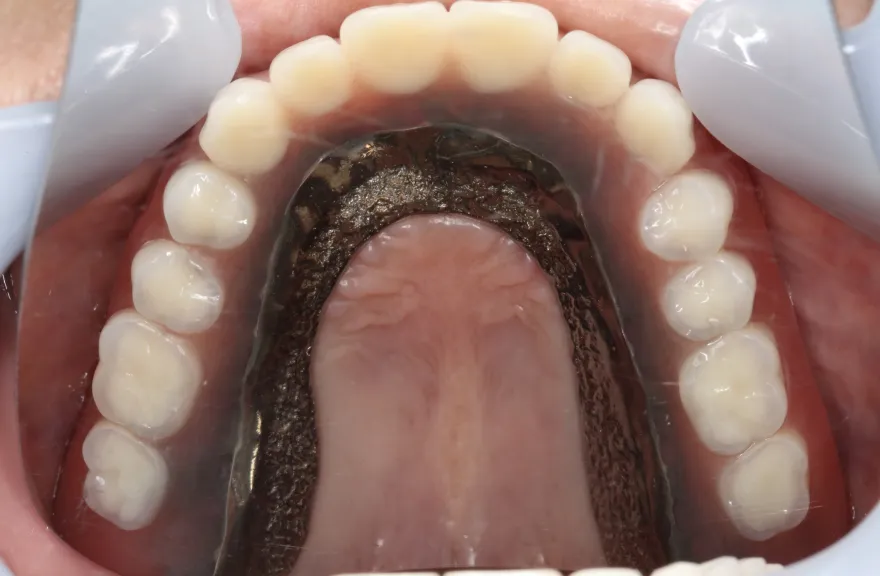

【治療例 2】金属を白くしたい63歳

右上の奥歯が取れたということで来院されました。

各所の金属は昔に治療されたもので、外してみるとどれも虫歯になっていました。

一つずつ虫歯治療を行い、インプラント治療、矯正治療を並行して行いました。 - 治療費用・方針

写真の通りに治療を終了いたしました。

各所虫歯に侵食されていましたが、歯を残すことができたのでインプラントの数をおさえることができました。

下の前歯が先天的に1本欠損しており、そのため噛み合わせを構築することが難しいケースでした。矯正治療を併用することで前歯と奥歯をバランスよく噛ませることに成功しました。